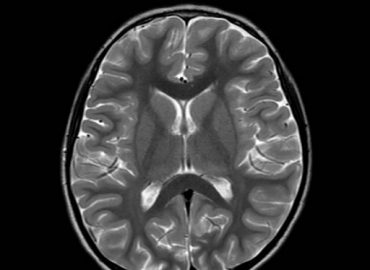

Paciente: femenina de 9 meses de edad Motivo de consulta: episodios convulsivos.

Niña de 5 años de edad, debut de crisis convulsiva.